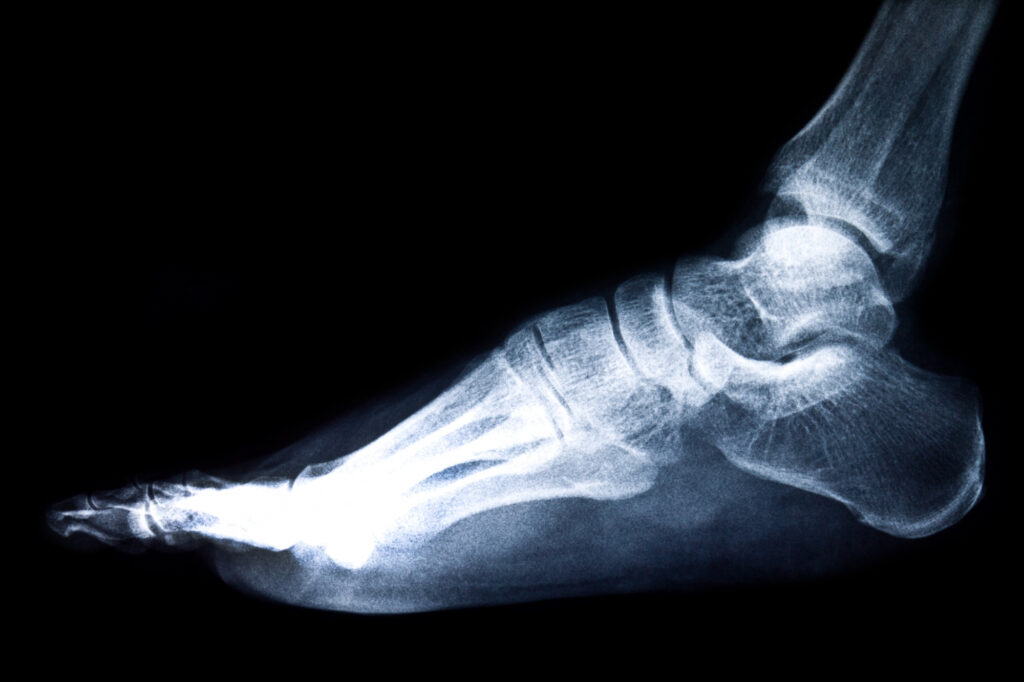

It’s made up of three main arches:

- The medial arch (the highest and most visible one, on the inner side of the foot)

- The lateral arch (lower and more stable, on the outer edge)

- The transverse arch (running side to side under the metatarsal heads)

All three work together to create elasticity, shock absorption, and propulsion.

When you walk, the arch flattens slightly to absorb impact.

When you push off to walk or jump, it springs back up to return energy.